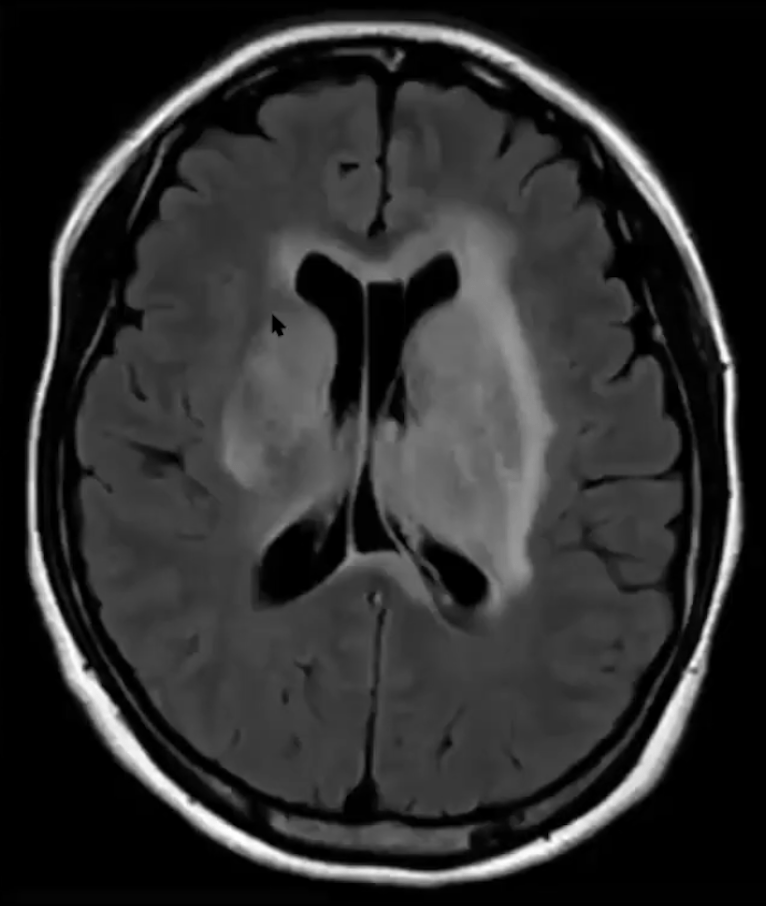

What vessel(s) caused this stroke?

Anterior Choroidal Artery

Interesting pearl: The homonymous hemianopsia appears as this:

Occlusion of which vessel(s) cause this stroke?

Artery of Percheron